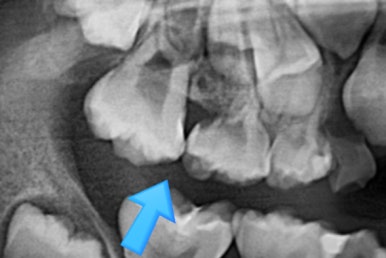

7개월 뒤 사진입니다.

해당 부위 어금니가 약간 나왔씁니다. 가장 간단하게 치료를 할 수 있는 상황이 되었네요.

매우 운이 좋았던 경우입니다.

어금니 방향이 서서히 변해가는 것을 보실 수 있을 것입니다.

단 3개월만에 제대로 못나오던 어금니 위치가 바로 잡혔습니다.

왼쪽이 부산어린이치아교정 키다리아저씨치과에서 치료하기 전 사진, 오른쪽이 후 사진입니다.

어금니가 잘 나온것을 확인할 수 있습니다.

왼쪽이 부산어린이치아교정 시행 전 X-ray, 오른쪽이 시행 후 X-ray 입니다.

3개월만에 많이 좋아졌습니다.